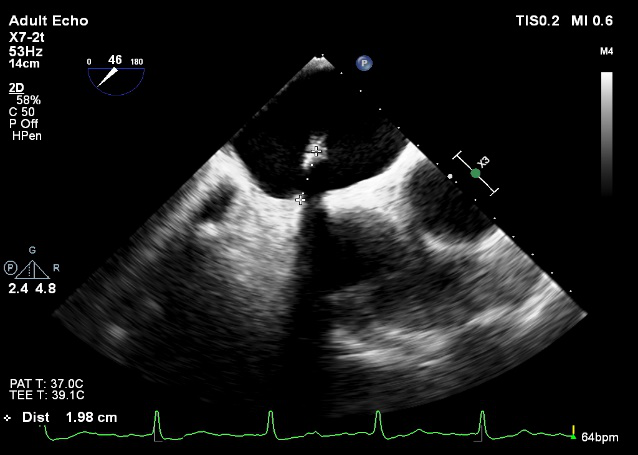

术中超声

确定房间隔穿刺点:靠后

2D视图下测量大鞘长度2cm

X-plane:下第夹子尝试捕获2区

X-plane:测量前叶长25mm,后叶长14.2mm

X-plane:计算前叶捕获长度8mm,后叶捕获长度7mm